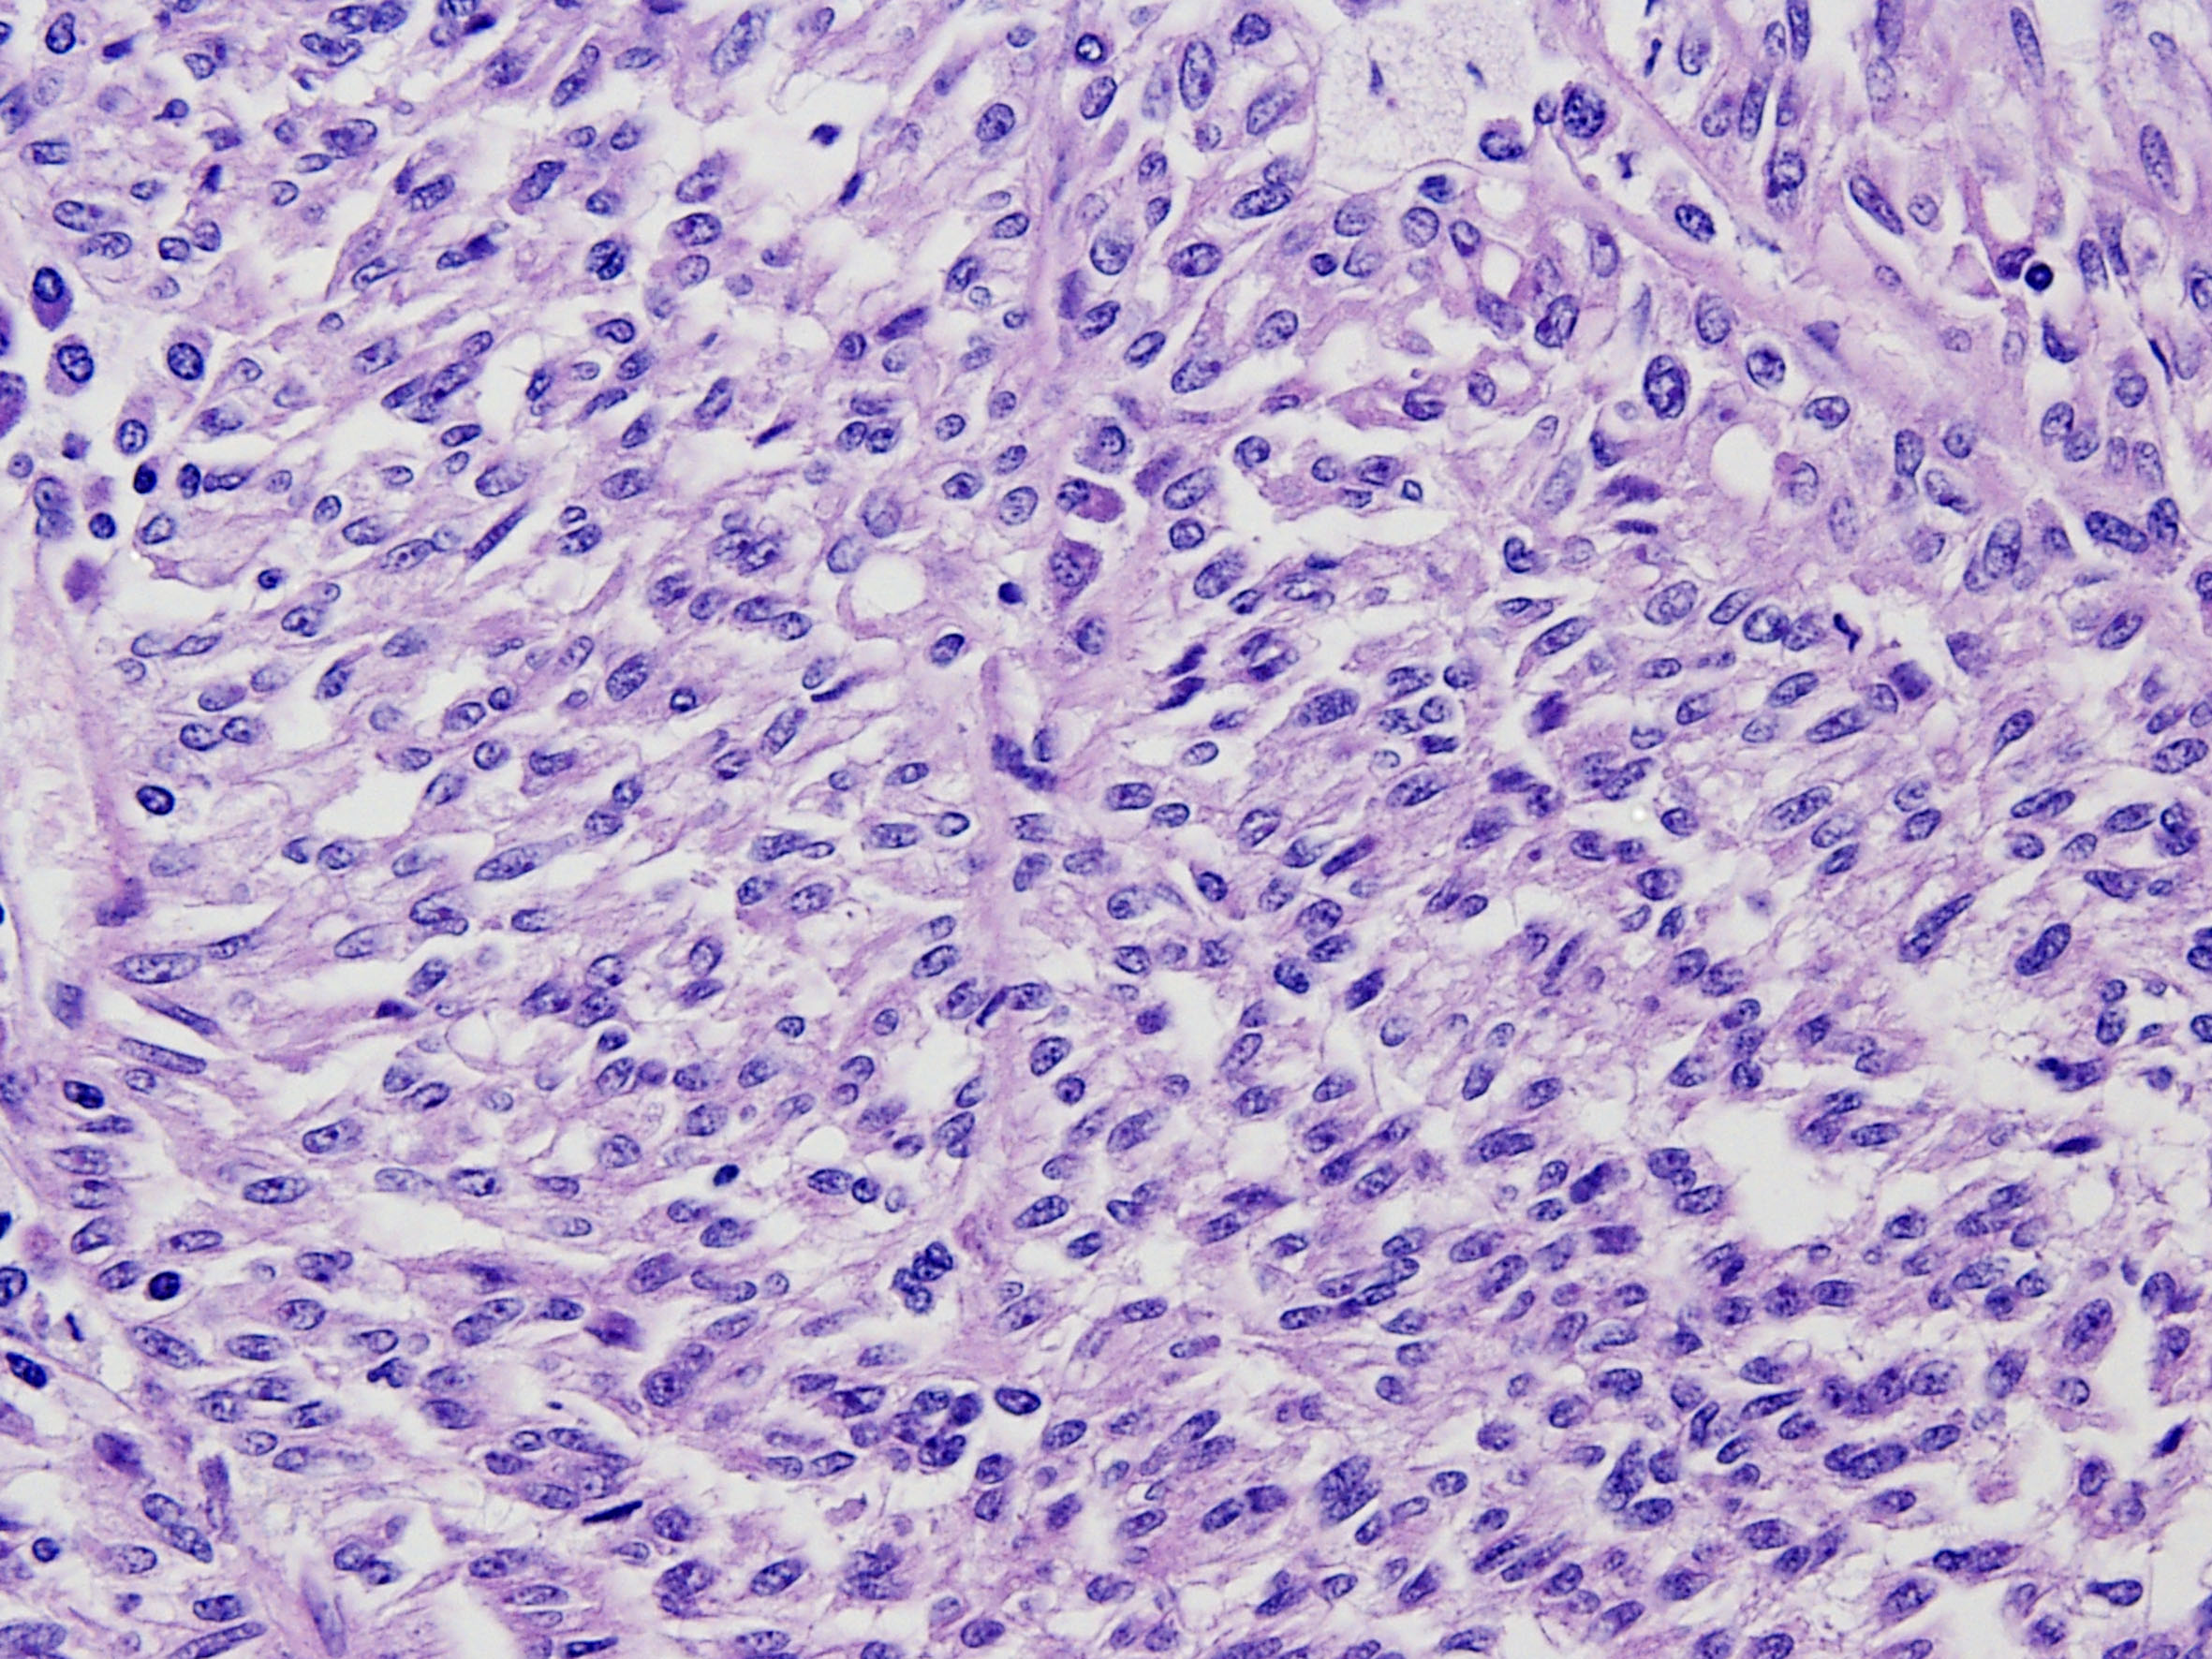

Classification of renal tumors

Case ID: 266